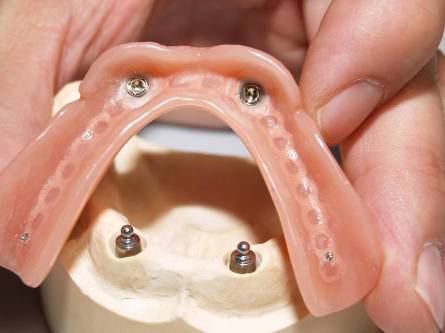

Pevné můstky – lepené nebo šroubované

Kulové attachmenty

Sub-Tec Locator®

S pomocí zubních implantátů můžeme díky různým kotevním systémům (třmeny, kulové hlavy, Locatory) zajistit stabilitu a držení protézy nebo při použití většího počtu implantátů zhotovit pevné náhrady – můstky nalepené nebo našroubované na pevno na implantáty.

S těmito typy náhrad můžeme dosáhnout perfektní funkci, výbornou estetiku, fonetiku a současně zajistit u pacienta možnost dobré hygienickou péče a čištění, která je pro životnost implantátů velice důležitá.